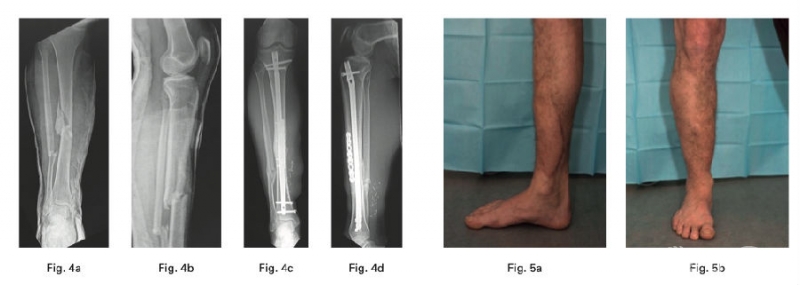

2、Hourani AI在一项病例系列中确定了使用mechanically relevant devitalized bone (ORDB)进行矫形重建是否与IIIB型开放性胫骨干骨折感染率增加相关,其结论为在IIIB型开放性胫骨干骨折治疗的情况下,在最终重建中使用ORDB是安全的。